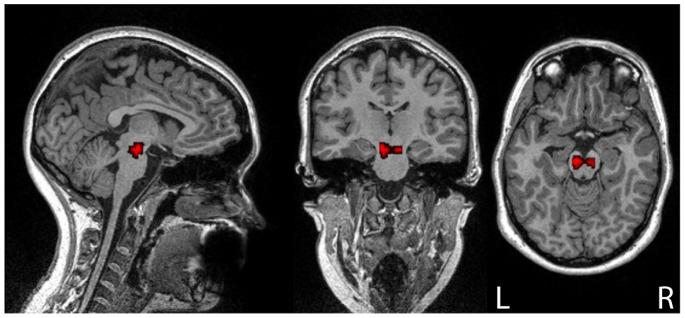

Here, we present an approach for identifying brainstem dopaminergic pathways using resting state functional MRI. In a group of healthy individuals, we searched for significant functional connectivity between dopamine-rich midbrain areas (substantia nigra; ventral tegmental area) and a striatal region (caudate) that was modulated by both a pharmacological challenge (the administration of the dopaminergic agonist bromocriptine) and a dopamine-sensitive cognitive trait (an individual's working memory capacity). A significant inverted-U shaped connectivity pattern was found in a subset of midbrain-striatal connections, demonstrating that resting state fMRI data is sufficiently powerful to identify brainstem neuromodulatory brain networks.

在此,我们提出一种利用静息态功能磁共振成像来识别脑干多巴胺能通路的方法。在一组健康个体中,我们探寻富含多巴胺的中脑区域(黑质;腹侧被盖区)与一个纹状体区域(尾状核)之间显著的功能连接,这种连接受到药理学激发(给予多巴胺能激动剂溴隐亭)和一种对多巴胺敏感的认知特质(个体的工作记忆能力)的调节。在中脑 - 纹状体连接的一个子集中发现了一种显著的倒U形连接模式,这表明静息态功能磁共振成像数据足以强大到能够识别脑干神经调节性脑网络。